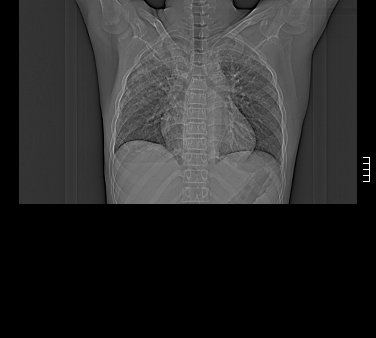

患者,男,17岁,系我院急诊科收治的一例百草枯中毒患者,做ct检查时,距离服药的时间为3天。上传与大家分享

补充:百草枯进入人体内主要分部于肺和骨骼,肺部损伤24小时内出现水肿,2-3天内出现急性呼吸窘迫综合征,1-2周内出现肺纤维化。(引自陈灏珠,实用内科学12版)